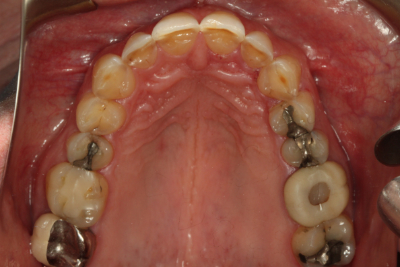

私たちの目標は常に、可能な限り最高の機能的結果を達成し、患者の目標を満たすために必要な最小限の歯科治療を行うことであるべきです。 ダレンは伝統的な歯科矯正に興味がなかったので、私たちは彼の機能の包囲の自由度を増加させ、前歯部咬合関係を改善するためにクリアアライナー療法から開始することを選択しました

歯科矯正はまた、歯の準備でより保守的にすることができました。 上顎切歯の舌側には、すでにかなりの歯質が磨耗していたため、削らなければならない歯質の量を最小限にしたかったのです。 また、矯正歯科では、前方誘導のために必要な下顎前歯の前処置や間接補綴を避けることができます。

矯正治療後、私たちは間接修復のために上顎弓を準備し、ダレンに仮の修復物を装着しました。 また、下顎切歯縁をダイレクトコンポジットで修復し、露出した象牙質を封鎖し、診断用ワックスアップから製作した熱可塑性ステントを用いて切歯面を整えました。 ステントを使用して切縁にダイレクトコンポジットを装着することで、時間を節約し、切縁の位置をより正確にすることができました。 その後、ダレンは歯周病専門医に送られ、歯肉の構造を修正しました。